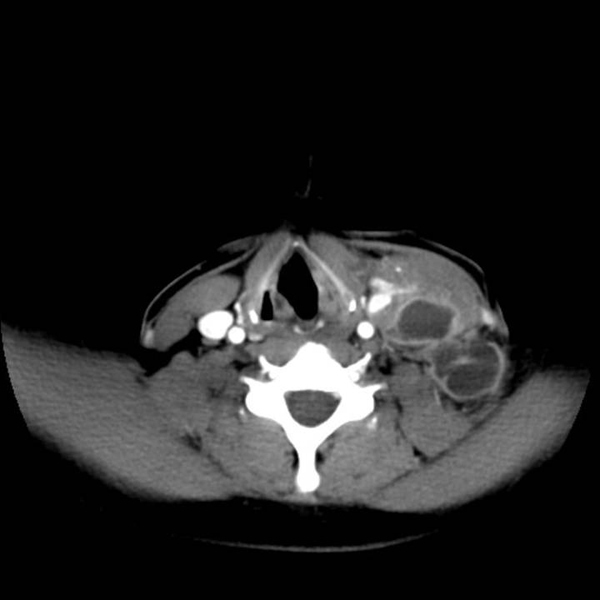

Tomodensitométrie cervicale révélant une masse latéro-cervicale gauche de 4 x 6 x 5 cm, à centre nécrotique.